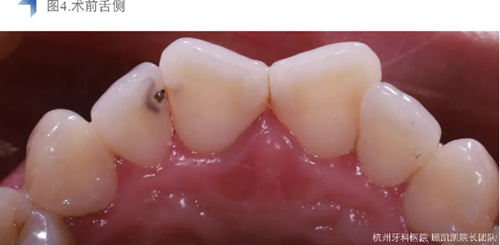

局麻橡皮障下去齲盡,極盡髓,iroot bp+蓋髓,上面覆蓋bisco硅酸鈣,流體樹脂洞型重建后貼面預備,排齦后Cerec Omincam光學取模,3D打印樹脂模型以檢查修整瓷貼面。